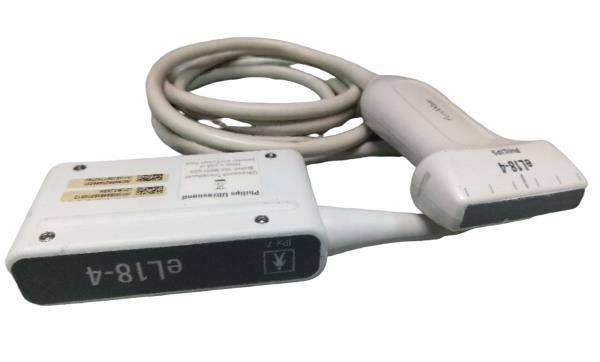

Description

ATL HDI 3500 w/ 2 Probes